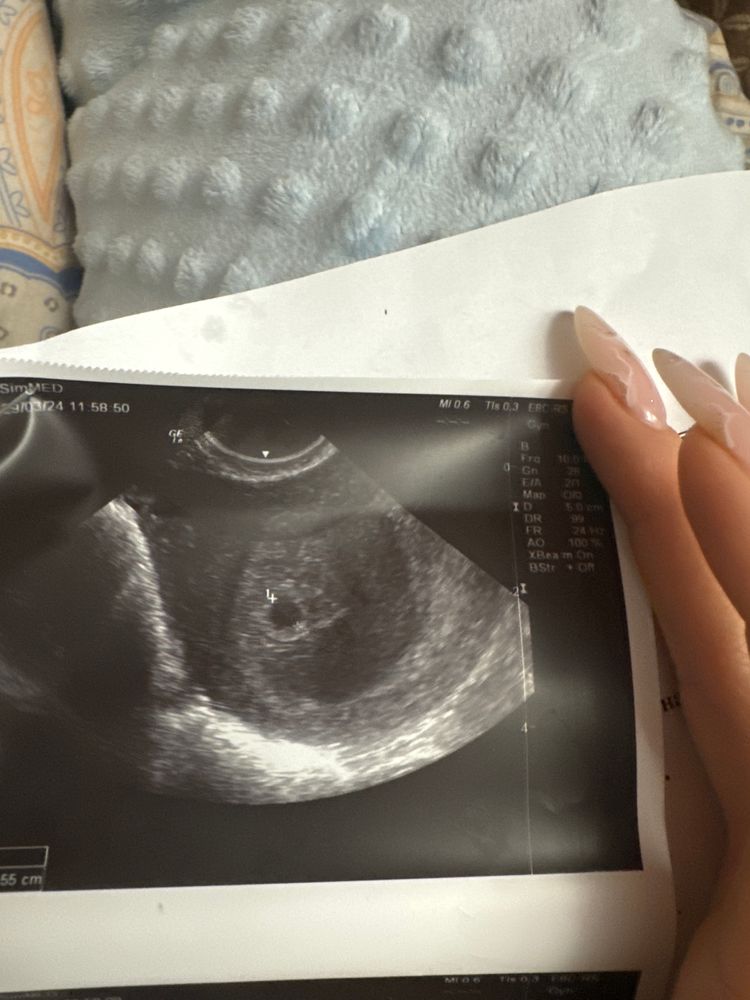

Девочки, была на узи. У меня большущая гематома. Пью дюфастон 3 раза в день, Виданол 3 раза в день, магне б6 по 2 таблетки 3 раза в день, свечи вибуркол 3 раза в день и когда чувствую, что напрягаеться живот неприятно, папаверин. Лежу, лежу неделю. Врач предлагал больницу, но выходные и лечение тоже самое. У меня с прошлого воскресения приключения тянуться, кровило ужасно. Пока на узи не сходила 100500 диагнозов наставила. Следующее узи через 10 дней. Переживаю, во первых эмбриончика не увидели, сердечко не услышали. Но делала узи ровно в 5 недель и понимаю рановато. Ну и гематома очень большая, врач сказал 50/50. Сдаю для себе хгч раз в 2-3 дня. Только так могу контролировать, что малыш живой🥺🥹 девочки, сколько при гематоме, при которой кровило вы пили кровоостанавливающие? У меня уже ттт совсем капельку мажет коричневым, вот совсем капельку. Пью просто уже неделю почти, по 3 в день. Переживаю